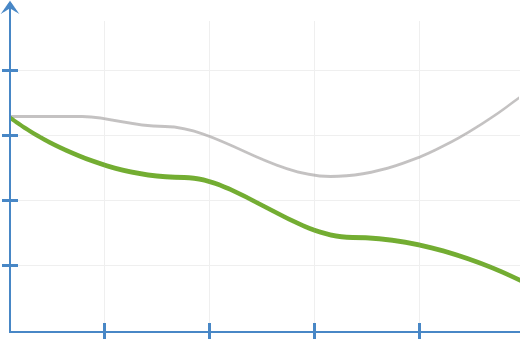

Динамика на

воспалените реакции

без ProstaFix

со ProstaFix

Откако ќе навлезат во телото,

активните компоненти

започнуваат да

дејствуваат

веднаш, елиминирајќи ја болката

и воспалението на клеточно ниво,

отстранувајќи ги

мускулните грчеви, елиминирајќи

ги тромбите и заздравувајќи ги мукозните мембрани.